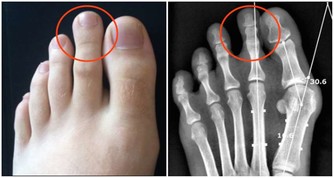

足貼變黑是在排毒?

真相:沾水就變黑,與毒無關

足貼是近兩年才火起來的“網紅”產品。“睡前將其貼上,第二天一早便會發現大量黑褐色的毒素被吸附出來”,類似的宣傳效應帶動了一大波養生達人追捧購買。

但實際上,這全是障眼法。

足貼中通常含有鐵粉、活性炭等物質,遇水便會變黑。一覺醒來發現足貼變黑,其實是因為腳底的汗液接觸了足貼裡的上述成分,而不是所謂的排毒。

指望貼個足貼就吸出毒素、油脂,簡直是天方夜譚,不信也罷。